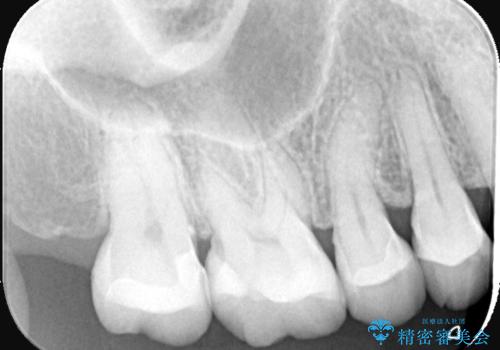

フロスなどの日常の清掃はもちろん不可欠ですが、メタルインレーより汚れが付着しずらいセラミックインレーにて今回は治療を行いました。

セラミックインレー装着時はラバーダムを使用して行っています。